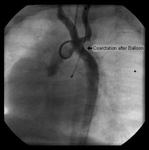

Aortic angiography in an infant after surgical reconstruction of the aortic arch shows marked narrowing at the distal aspect of the surgical repair

From the personal collection of Jeffrey Gossett, MD, Children's Memorial Hospital, Northwestern University, Chicago; used with permission

Balloon angioplasty of the narrowed region leads to complete resolution of the obstruction